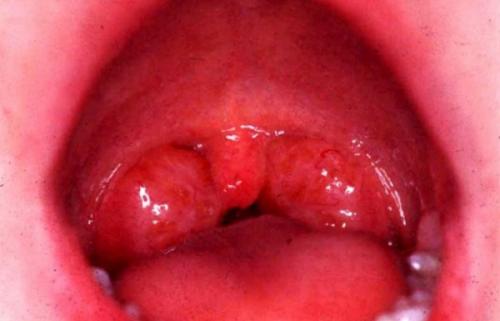

- Катаральная форма проявляется умеренными симптомами интоксикации, субфебрильной гипертермией, болью в горле. На этом этапе врач при осмотре горла выявляет покраснение, отечность, инфильтрацию миндалин. При раннем начале лечения удается избежать приема антибиотиков, прогрессии заболевания. Симптомы регрессируют уже через 3 дня.

Первое проявление – отечность слизистой, разбухание глоточного кольца, боль при глотании. Гланды при этом значительно воспалены – увеличены в размерах и имеют ярко-красный цвет. Начинают ныть шейные лимфоузлы, при пальпации шеи прощупываются увеличенные узелки.